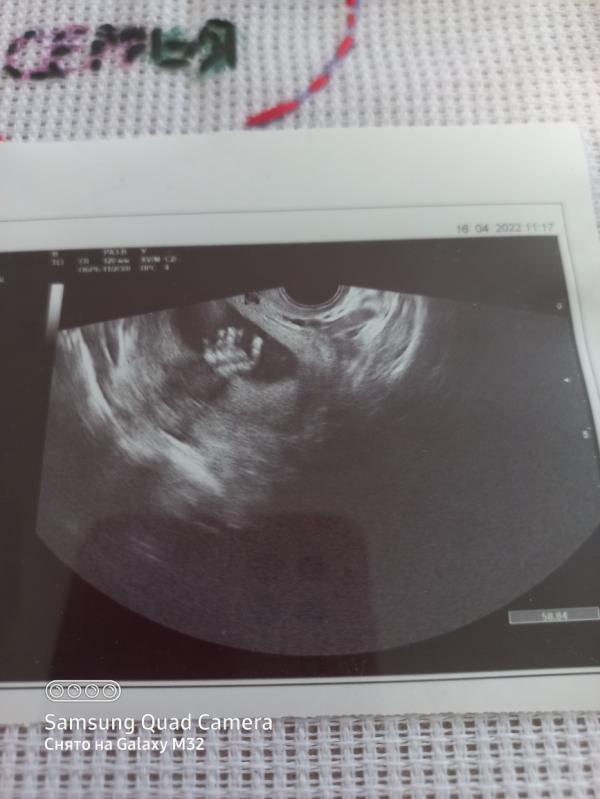

Наша вторая девочка 🤗

Только доктор которая делала нам 2 скрининг ставит гиперплазия плаценты. Это что то страшное? До приема к доктору далеко. А читать в интернете не хочу. Кто с таким сталкивался?